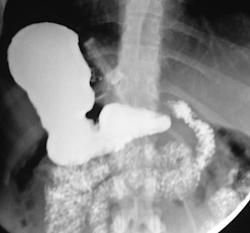

Не, тоже не то. верхние снимки выполнены в положении стоя, последние в положении лёжа. Подсказка есть в самих снимках. Я извиняюсь за качество; у меня флюроскопия записывается в виде цифрового видео, пришлось "ловить стоп-кадры для публикации.

Общая брыжейка-да, наиболее вероятно. Но не это главная причина, по которой я опубликовал данное наблюдение. Инверсии нет; я уже указал что снимки это стоп-кадры с записи флюорографического исследования, поэтому получается зеркальное изображение. В случае инверсии, я конечно бы разместил обзорный снимок. Патология исключительно в желудке, и это наглядно видно. Я понимаю что "играю-немного-не-по-честному", но я сразу указал что это именно загадка. "Подсказка"-это не дренаж; пациентка пришла амбулаторно.

Да, в настоящее время считается одним из самых эффективных методов. Показан пациентам с 3ей и 4ой степенью ожирения. Принцип простой; на проксимальный сегмент желудка накидывается манжетка; которая как петля захватывает желудок; как бы создавая искусственный стеноз на уровне петли и формируя из верхней части маленький резервуар. Этот резервуар быстро наполняется малым количеством пищи; и пациент чувствует насыщение. Люди за год теряют до 30-40 кг. При помощи зонда и имплантированного под кожу аппликатора с физиологическим раствором, можно контролировать степень сужения (диаметра петли). Одно из самых распространённых осложнений при таких процедурах - синдром "соскальзывания" петли. Slipped gastric band syndrome.

Не, тоже не то. верхние снимки выполнены в положении стоя, последние в положении лёжа. Подсказка есть в самих снимках.

Общая брыжейка-да, наиболее вероятно. Но не это главная причина, по которой я опубликовал данное наблюдение. Инверсии нет; я уже указал что снимки это стоп-кадры с записи флюорографического исследования, поэтому получается зеркальное изображение. В случае инверсии, я конечно бы разместил обзорный снимок.

Патология исключительно в желудке, и это наглядно видно. Я понимаю что "играю-немного-не-по-честному", но я сразу указал что это именно загадка. "Подсказка"-это не дренаж; пациентка пришла амбулаторно.

Предлагаю ознакомиться с этими картинками; они многое пояснят! Но, в моём наблюдении не просто ятрогения, но есть осложнение, постарайтесь логически догадаться какое.

Получается муфта соскользнула с желудка и уперлась в диафрагму, тем самым наверное поддавив абдоминальный сегмент пищевода